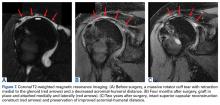

Before surgery, 4 patients had Goutallier 17 stage 4 rotator cuff muscle degeneration, 2 had stage 3 degeneration, and 2 had stage 2 degeneration. Throughout the follow-up period, US was as effective as MRI in determining graft integrity, graft thickness, and greater tuberosity fixation. Therefore, the SCRs were assessed primarily with US. MRI was ordered only if a failure was suspected or if the patient had some form of trauma. A total of 7 MRIs were ordered for 5 of the 8 patients in the study. The graft was intact in 4 of the 5 ( Figures 7A-7C ) and ruptured in the fifth.

One patient fell just after surgery. The graft was intact, but the infraspinatus was torn. As this patient was doing well, there was no need for treatment. Two patients were in motor vehicle accidents. One was found to have a detached glenoid-sided graft, but refused treatment because symptoms were tolerable (this patient had been improving before the accident). The other patient, who had an MRI-confirmed rupture of the graft midsubstance, was considering revision SCR or RTSA.Discussion